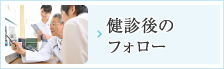

PET検査とは

「PET」とは、「Positron Emission Tomography」の頭文字を取って「ペット」と発音され、日本語では「陽電子放出断層撮影法」と訳されます。アイソトープ検査の一つで、陽電子を放出する薬剤を体内に注射して検査を行います。

PET検査の特徴

- 比較的小さながんの発見に優れているためがんの早期発見に有用である。

- 一度に全身の検査が可能である。

PET-CT検査の有効性

- PET-CTで使用される薬剤(FDG)はブドウ糖の一種であり、副作用の報告はありません。また、「FDG」の放射線が半分になる時間(半減期)は非常に短く、薬剤の大部分は尿から排泄されます。翌日にはほとんど体内に残りませんのでご安心ください。

- 「FDG」を用いたPET-CT検査では、ブドウ糖が細胞に取り込まれる過程である「糖代謝」を画像にしているため、「糖代謝」のあまり盛んでないがんなど、種類によってはあまり得意としないがんもあります。また、腎臓や膀胱といった正常でも薬剤が集まってしまう部位(生理的集積部位)の診断には向いていません。そのため、他の検査と組み合わせることによって、存在部位や範囲、重症度がより明確に分かるようになることがあります。以上の点から、PET-CT検査だけでなく他の最適な検査法を併用して最良の診断を受けることをおすすめします。